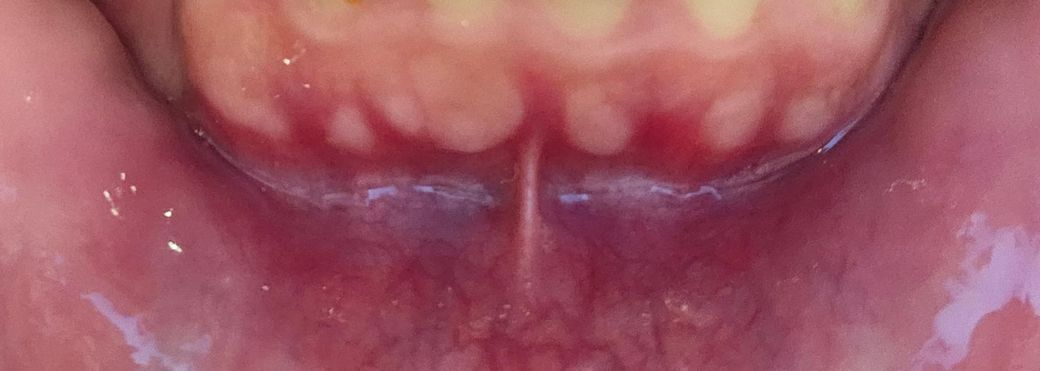

잇몸이 튀어나오는데 병인지 궁금해요

하얗게 보이는 부분을 만져보면 치아 뿌리같아요

원래 이랬는지를 모르겠는데 어떤 병인건가요??

• 1번 째 사진

잇몸뼈가 자라서 튀어나온것입니다. 치조골융기라고 하는데 앞으로 더 커질 수도 있지만 딱히 병은 아니라서 불편하지 않으시면 그냥 놔두시면 됩니다. 나중에 틀니를 사용하게 됐을 때 불편할 것 같으면 좀 갈아내야할 수도 있기는 합니다.

사진으로 보이는 부분은 치조골이 밖으로 자라나와 있어 잇몸이 얇고 혈액이 적게 있어 밝게 보이는것입니다.

정상적인 잇몸이기 때문에 걱정하지 않아도 됩니다.

치아뿌리 아니고 잇몸뼈(alveolar bone)라고 보시면 됩니다 특별히 치료가 필요하진 않습니다 저작력 등에 의해 골이 증식할 수 있습니다